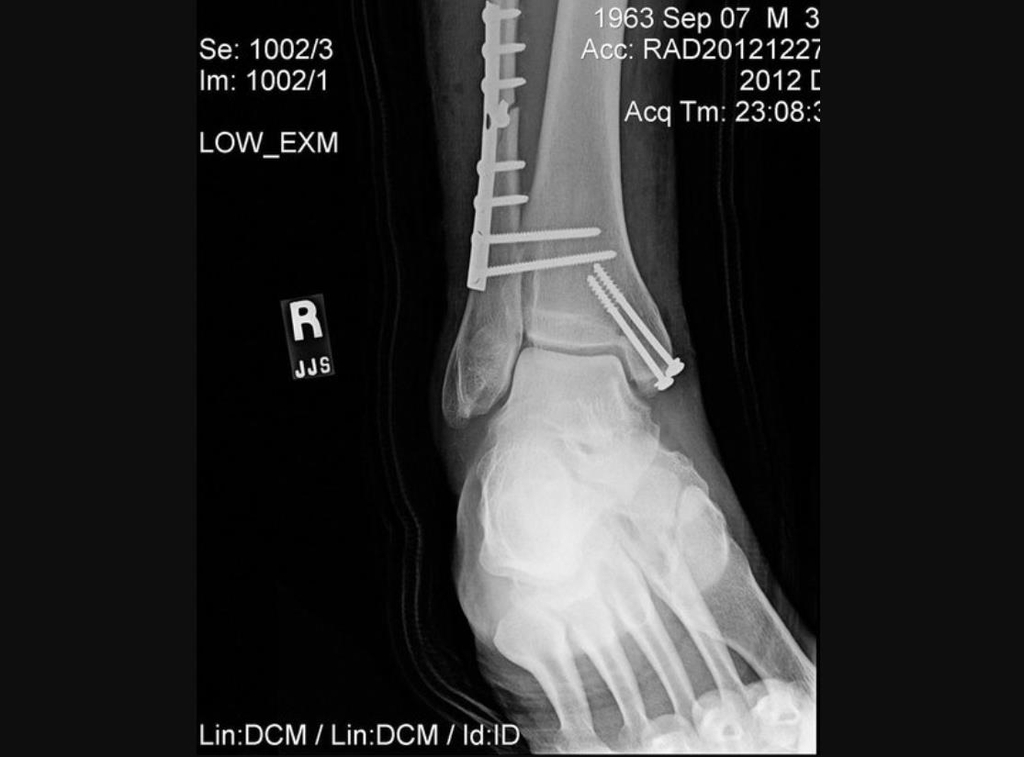

| ▲ 수술용 나사와 핀으로 뼈를 고정한 모습 [우즈 수술과 관련 없음, 트위터 게시물 캡처, 재판매 및 DB 금지] |

의료진은 철심을 박아 무릎 아래 두 개의 긴 뼈인 정강이뼈와 종아리뼈를 고정했다.

또 발과 발목뼈는 수술용 나사와 핀으로 안정시켰다.

나사는 일반적으로 골절된 뼈를 접합하는 데 사용되고, 핀은 탈구됐을 수 있는 관절을 바로 잡는 데 쓰인다.